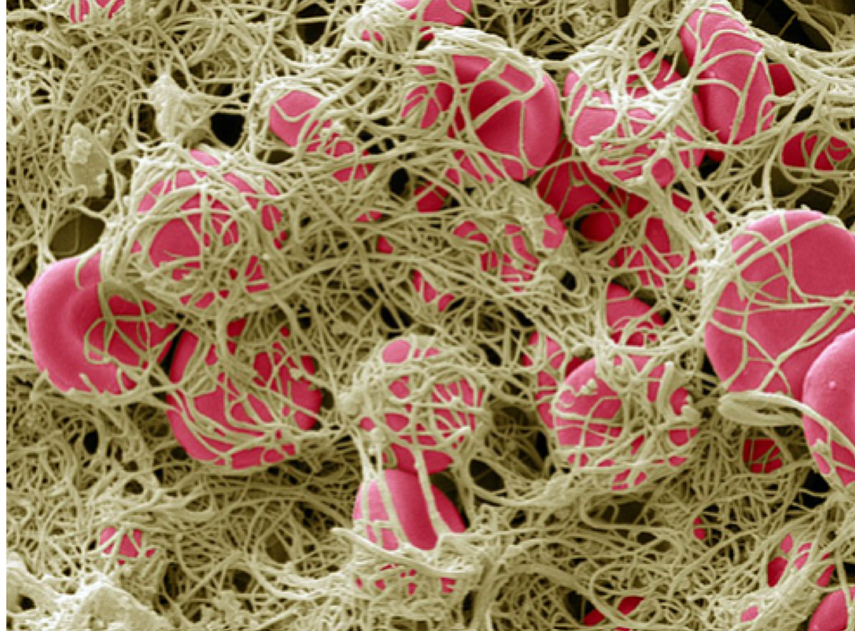

What’s Causing the “Killer” Vascular Blood Clots?

Throughout the world, doctors are putting the Covid vaccine under the microscope, along with human blood from vaccinated people, and discovering the most astoundingly disgusting results that prove that pharmaceutical companies are lacing jabs with nano-metals, graphene and iron oxide nano-structures, and many other substances of “unknown” origin.

These substances are accumulating in blood vessels as they self-organize and self-replicate with the magnetic and electrically conductive materials found in the vaccines that are being used by the pre-programmed graphene oxide to build unidentifiable structures in blood vessels and tissue that block blood flow creating strokes and heart attacks. These “structures” have also been analyzed and found to contain the same substances.

In an article from The Expose entitled: Covid Injection Aftermath: Study finds 94% of “Vaccine” Recipients have Pre-Blood Clot Formations and Foreign Particles, by Rhonda Wilson, on 8/24/2022 the author states: An Italian study published two weeks ago in the International Journal of Vaccine Theory, Practice, and Research revealed almost everyone who had been injected had abnormalities after Covid vaXXXination. In 94% of vaXXXinated blood, there was an aggregation of red blood cells and the presence of particles of various shapes and sizes. The study began in March 2021. Using dark-field microscopy, the researchers analyzed blood samples from 1,006 referred to the Giovannini Biodiagnostic Centre for various disorders after being injected with Pfizer/BioNTech or Moderna mRNA vaccines.

In the study, authors noted that the vaccines are purported to contain at least the spike protein from SARS-CoV-2 but are known also to contain foreign particles. “Among those foreign components are metallic objects as demonstrated previously in this journal by Lee et al. (2022) which are confirmed in our results.” Of the 1,006 cases analyzed, only 58 – equal to 5.77% of the total – presented a completely normal hematological picture upon microscopic analysis after the last mRNA injection with either the Moderna or Pfizer vaccine. The blood of 948 – 94% of the study’s participants – showed aggregation of red blood cells and the presence of particles of various shapes and sizes of unclear origin one month after the mRNA injection.

Blood clots found by morticians have been sent all over the world to be studied by independent teams.

The only thing that is for sure is that something is taking the injected metals and building them into “killer clots” throughout the body.

These clots have substances and structures inside of them that are “unidentifiable” and cannot be explained by anyone. But they are obviously designed to kill the host body that receives the injections.

As red blood cells are poisoned and destroyed by graphene oxide, luciferase, PEG, Parasites and genetically modified RNADNA genetic/microzymian fragments from mouse, bat, monkey and aborted fetuses contained in the CoVid-19 so-called vaccines all blood counts begin to dangerously drop!

This includes dangerously low red blood cell counts, hemoglobin, hematocrit, white blood cell counts, including neutrophils, basophils, eosinophils, T and B lymphocytes all begin to drop below normal ranges because people are being poisoned by each toxic injection.

The OH (hydroxy) groups can then split off a proton which leaves a negative charge affecting the whole graphene sheet and making it highly acidic and damaging to red blood cells. It also is incredibly sharp and acts like razor blades cutting blood vessels, tissue, and organs. Self-organizing GO tubes and sheets can block capillaries and arteries, with devastating effects when this occurs in the heart and lungs.

Graphene Oxide inside the body causes thrombogenicity, blood clotting, post inflammatory syndrome or systemic or multi-organ inflammations, causes alteration of the immune system, collapse of the immune system, cytokine storms, neurodegeneration, and mutagenic effects changing the DNA of the host.